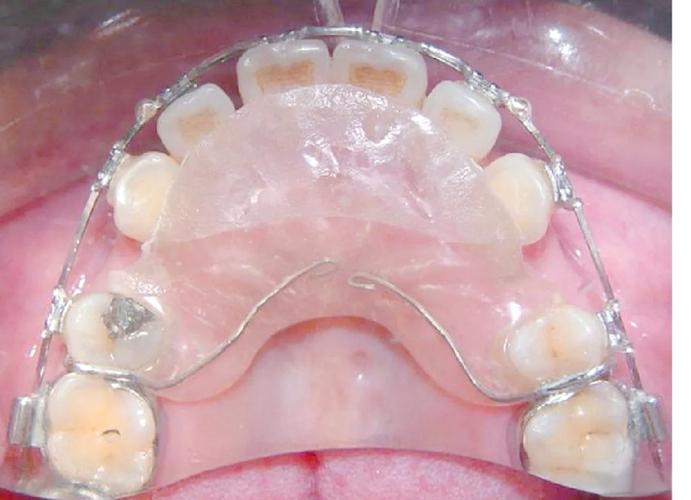

在技术设备与诊疗流程上,三甲医院同样具备不可替代的优势,正畸的核心是“精准”,而精准依赖先进设备,三甲医院普遍配备数字化口内扫描仪(替代传统取模,提升舒适度和精度)、CBCT(三维锥形束CT,可清晰显示牙根位置、骨量及神经管)、数字化头影测量系统(分析骨骼与牙齿的协调性)等高端设备,实现“数据采集-方案设计-效果预测”的全流程数字化,对于骨性龅牙患者,传统正畸可能需配合正颌手术,而三甲医院可通过三维头影测量模拟手术效果,提前规划牙齿移动路径,实现“正畸-正颌”联合治疗的最优化,三甲医院严格执行医疗质量控制标准,每个正畸方案需经过科室病例讨论,复杂病例甚至需多学科会诊(如联合牙周科、修复科、外科),确保方案科学可行,这种“团队作战”模式,是多数私立机构难以复制的。